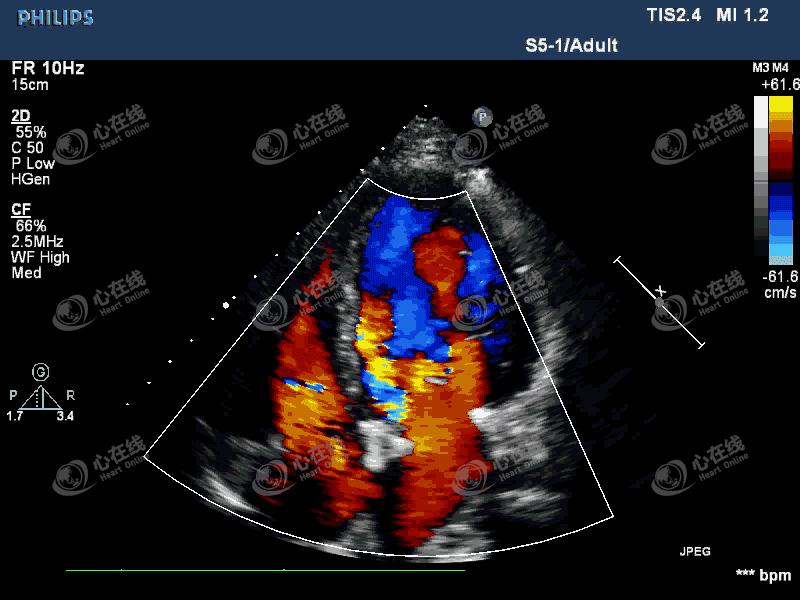

图2 左室长轴切面:彩色多普勒示,机械瓣瓣环外侧可见中量血流信号进入左室,另可见机械瓣中心性反流信号。主动脉根部膜样回声破口处可见血流信号,来自主动脉,并穿梭于该无回声区内。

图3 四腔心切面:彩色多普勒显示中量偏心性反流信号,起自主动脉瓣机械瓣环外侧。